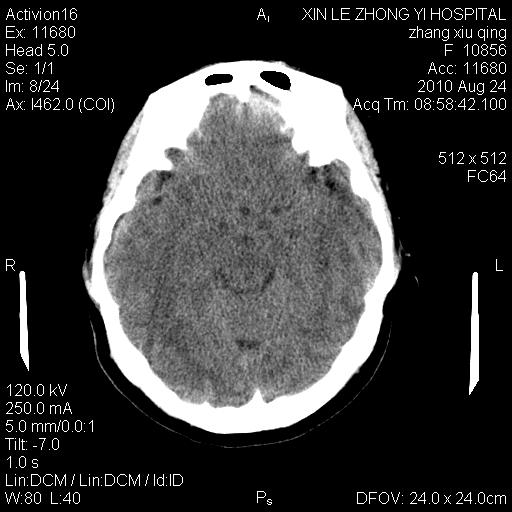

标题: CT28569:看看鞍上池正常吗 [打印本页]

标题: CT28569:看看鞍上池正常吗

女 24 偶有头晕

怎么这么多伪影?我感觉没什么特别异常哦,是不是伪影所至呀

未见明显异常,必要时可作mri

伪影干扰下,所见无水肿、无占位,建议定期复查。